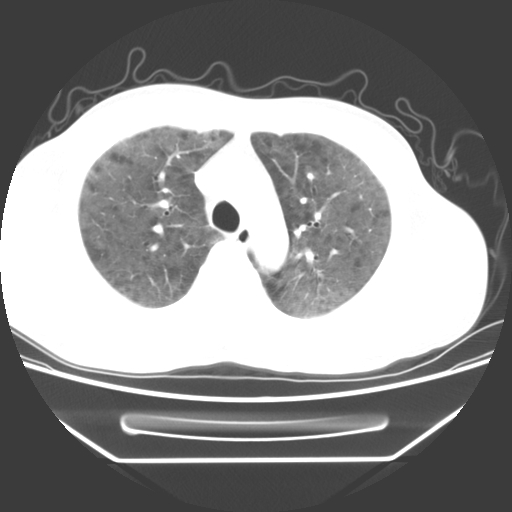

病人55岁,咳嗽,胸闷

忘了传病史了,病人55岁,咳嗽,胸闷

两肺部呈“毛玻璃”状改变,原因待查考虑感染性病变

病人是否发烧,两肺“磨玻璃”影,其间见空气支气管征和碎路石征。考虑肺泡蛋白沉着症。

两肺广泛对称磨玻璃样影,密度不均,考虑机遇性肺部感染。

双肺弥漫磨玻璃样病变,病史很重要。有感冒或发烧史,甲流不除外。无发烧可考虑肺泡蛋白沉积,但肺泡蛋白沉积边缘往往较清晰,与正常肺组织分界清晰

两肺弥漫间质性病变,考虑肺泡蛋白沉着症。建议进一步检查。